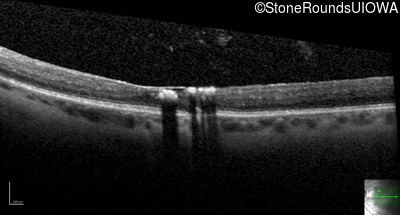

Autosomal Dominant Vitreoretinochoroidopathy (III4A)

Age at visit: 47 years

This 47 year old woman began wearing glasses at age 5 and had cataract surgery at age 32. At that time her doctor noticed a retinal abnormality.

Autosomal Dominant Vitreoretinochoroidopathy BEST1 Tyr72Asn TAC>AAC   AD